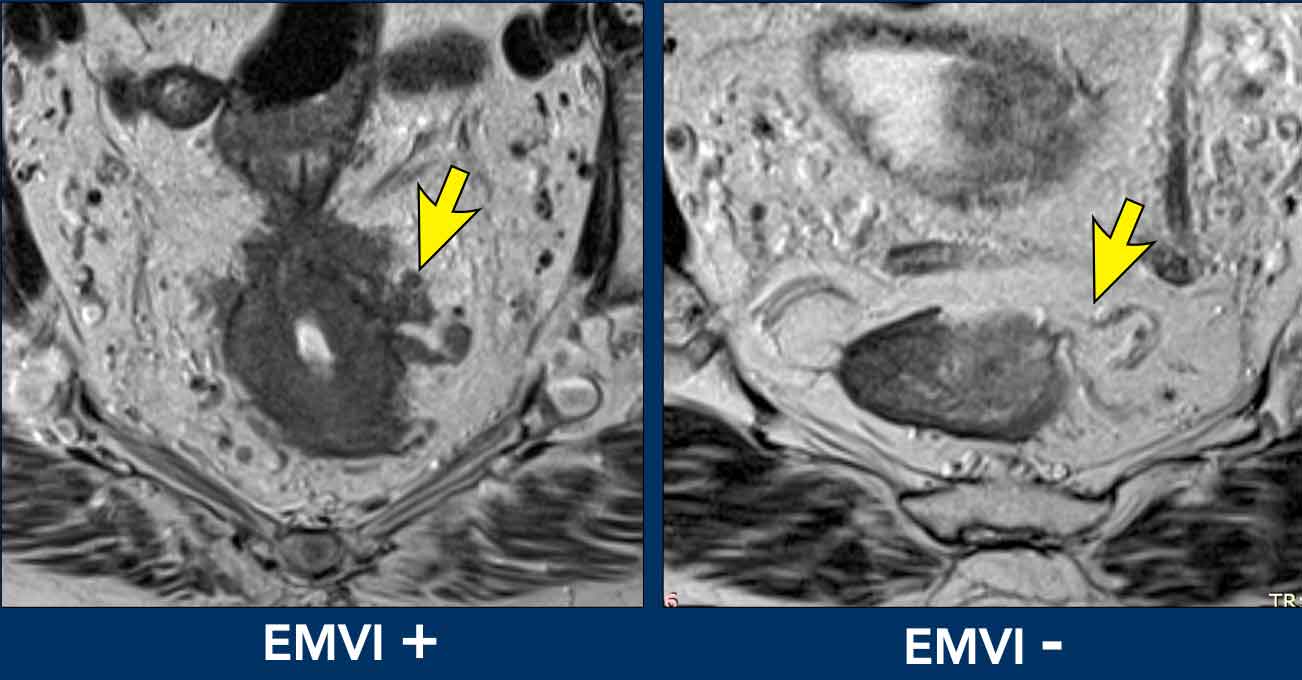

Extramural vascular invasion (EMVI)

EMVI is a risk factor for recurrent disease, metastases and impaired overall survival.

EMVI is suspected if we see tumor-signal extending into an adjacent vessel, when the vessel is expanded by tumor, or if the tumor disrupts the vessel borders (illustration).

EMVI can be graded as follows [ref]:

• 0 = no nodular extension beyond the muscularis propria and no vessels adjacent to areas of tumor extension

• 1 = Minimal nodular extension or stranding, not in the vicinity of vascular structures

• 2 = stranding in the vicinity of extramural vessels, with vessel of normal caliber and no tumor signal extending into the vessels

• 3 = tumor signal extending into vessels, with normal or slightly expanded vessel contour

• 4 = tumor signal extending into vessels with clear disruption of vessel contour and/or nodular expansion of the vessels

Grades 3 and 4 should be reported as EMVI+ disease.

Grades 0-2 as EMVI-.

Example

This image demonstrates EMVI+ disease, showing tumor signal extending into an adjacent vessel, resulting in vessel expansion and contour disruption.

Pitfall: overstaging of EMVI

Normal perirectal vessels of varying diameters often radiate outward from the muscularis propria into the mesorectal fat.

Do not misinterpret these as EMVI unless there is clear tumor invasion—defined as tumor signal extending into, expanding, or disrupting the vessel contour.

Key Assessment Tip

Evaluate the tumor’s circumferential location within the rectal wall.

Vessels not originating from the tumor attachment site should never be classified as EMVI, regardless of prominence.

Image comparison

• Left (EMVI+): Tumor signal clearly extends into adjacent vessels, disrupting their contours.

• Right (EMVI-): Vessels maintain smooth contours with no tumor signal present.